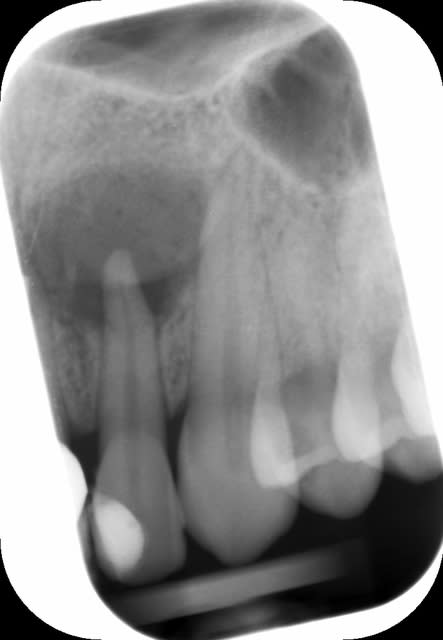

46 - fig 1,2 situation initiale

Fase du traitement: seule visite 2h

- percussion - positive

- teste du vitalité - négative

NaOCl 5% - l'irrigation et l'activation par ultrasons

chaud condensation de gutta-percha

build-up